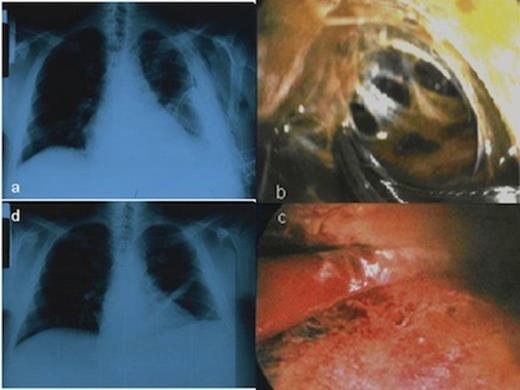

A 38-year-old man with a background history of alcoholic cirrhosis was referred to our department with HH one year ago. Two weeks before that, the patient was admitted in a secondary health care setting due to sudden dyspnea and ascites. The chest X-Ray (CXR) showed massive pleural effusion in the left hemithorax and a chest tube was erroneously inserted and drained transudative fluid (˜3l/day) (Figure 1a). The patient was diagnosed with HH. On day 10, the patient presented with fever; he was treated with antibiotics and was referred to our department for further management of his HH.

CXR showing the HH and the chest tube in the left hemithorax before the MT, b. Multiloculated thoracic empyema as a complication of HH, c. Disruption of fibrinous adhesions and debridement of parietal and visceral pleura, d. Chest X-ray following MT showed no recurrence of the hydrothorax

The patient was classified as Child-Pugh C category. Heart ultrasound was normal. We decided to perform talc pleurodesis by MT with local anesthesia in order to avoid potential hepatotoxic effects caused by drugs used in general anesthesia. Local anesthesia was performed with lidocaine and ropivacaine hydrochloride while midazolam, fentanyl citrate and propofol drips were used for sedation. The chest tube was removed and the thoracoscope entered the pleural cavity through a port. One additional incision (~1 cm) was made for instruments’ insertion. Surprisingly, inspection of the pleural cavity revealed multiloculated thoracic empyema. Fibrinous adhesions were disrupted and parietal and visceral pleura were debrided in order to unify the pleural space. The complicated pleural effusion was evacuated (Figure 1b, c). A segment from parietal pleura was sent for culture and pleural fluid was also sent for culture and biochemical analysis. Finally, talc pleurodesis was performed, so the lung parenchyma re-expanded with obliteration of the pleural cavity. Postoperatively, the patient had leukocytosis and fever. Pleural fluid was a transudate infected by Staphylococcus aureus sensitive to azithromycin which was administered to the patient. CXR following MT showed no recurrence of the hydrothorax (Figure 1d). Figure 2 shows the gradual improvement of patient's serum test levels during his hospital stay. The patient was discharged on the 8th postoperative day in good condition and did not have any recurrence in a follow-up of 4 months after the procedure.